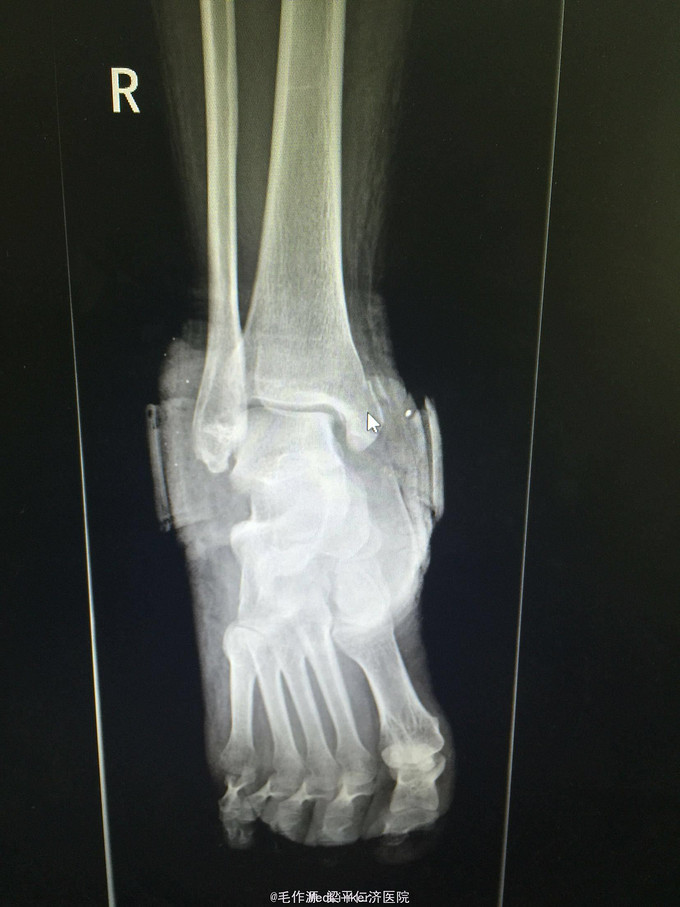

患者女,48岁,因“摔伤致右踝关节疼痛、畸形伴活动受限7天”入院。

右踝关节肿胀明显,畸形,可见大量皮肤瘀斑形成,局部压痛明显,可扪及骨擦感及骨擦音,踝关节活动因负痛不能活动,足背动脉可扪及,肢体远端血运及感觉无异常。 右踝关节DR正侧位提示:右侧内外后踝骨折伴踝关节半脱位。

右三踝骨折伴踝关节半脱位 入院后予以完善相关检查,手法复位纠正脱位,右下肢石膏外固定,抬高患肢,予以消肿、止痛等对症治疗。

患者骨折移位明显,有手术指征,经与患者及家属沟通后,准备完善相关检查,若无特殊手术禁忌,拟于近日行“右内外踝骨折切开复位内固定术”。